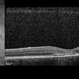

- Imaging device

-

Fundus camera

Optos Fundus Camera - Description

- 65-year-old-male with curtain/veil over vision for two days.